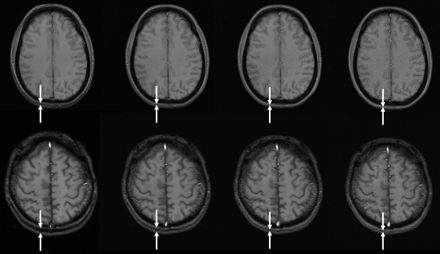

Chemical shift artifacts at different bandwidths at 1.5 (upper row: TR, 172 ms; TE, 9 ms; field of view [FOV], 220 × 220 mm2; matrix, 256 × 192) and 3T (lower row: TR, 206 ms; TE, 10 ms; section thickness, 5 mm; FOV, 220 × 220 mm2; matrix, 256 × 192). Bandwidth increases from left to right (60, 120, 240, 480 Hz/pixel), resulting in chemical shift of 7.4, 3.7, 1.9, and 0.9 pixels, respectively, at 3T, and half of these values at 1.5T. Note the double line of the occipital subcutaneous tissue at lower bandwidths (between white arrows). Of note also is the increasing noise at higher bandwidths.

Consequently, increasing bandwidth reduces part of the extra signal intensity provided from imaging at 3T. In other words, doubling bandwidth to keep chemical shift effects constant between 1.5T and 3T reduces the original signal intensity gain obtained from 3T when compared with 1.5T from 200% to 141%.